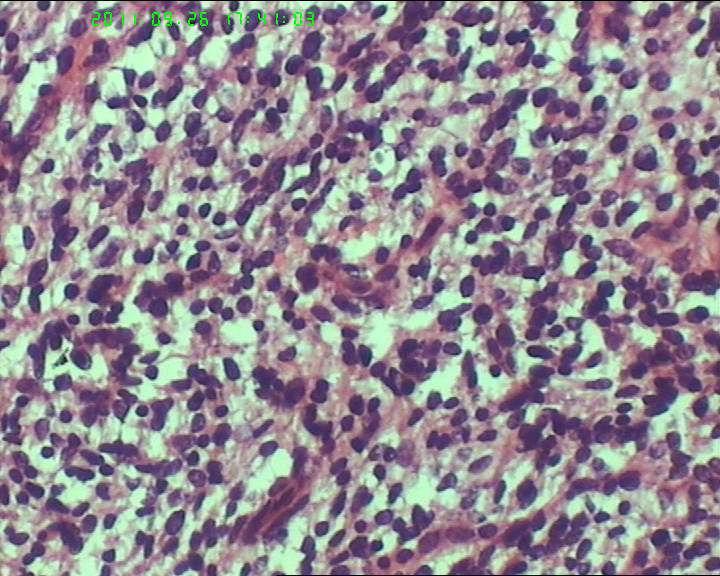

灰白不整形肿物一个,大小18*15*9cm,表面结节状,包膜完整,切面灰白,中央可见坏死区,质软,范围5*4cm。其余切面多彩 部分半透明状 质中。

鉴别诊断排排队:1、GIST,2、MPNST,3、去分化脂肪肉瘤,4、恶性间皮瘤,5、恶性SFT,6、平肉

主要考虑前二者。CD34,CD117,S-100,BCL-2,SMA, D2-40,CR, VIM. 结果如何?请楼主揭谜底吧。